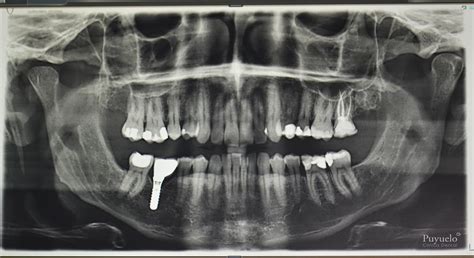

Una ortopantomografía es un tipo de radiografía que proporciona una visión completa de ambas mandíbulas (superior e inferior), todos los dientes y las estructuras adyacentes, como los senos maxilares y las articulaciones temporomandibulares.

- Cobertura Completa: Ofrece una visión completa de ambas mandíbulas, todos los dientes y las estructuras adyacentes.

- Diagnóstico Integral: Permite identificar una amplia gama de problemas dentales, incluyendo caries, enfermedades periodontales, quistes, tumores y anormalidades óseas.

- Evaluación Preoperatoria: Es esencial para la planificación de tratamientos como la colocación de implantes dentales, la extracción de dientes (especialmente las muelas del juicio) y la evaluación ortodóncica.